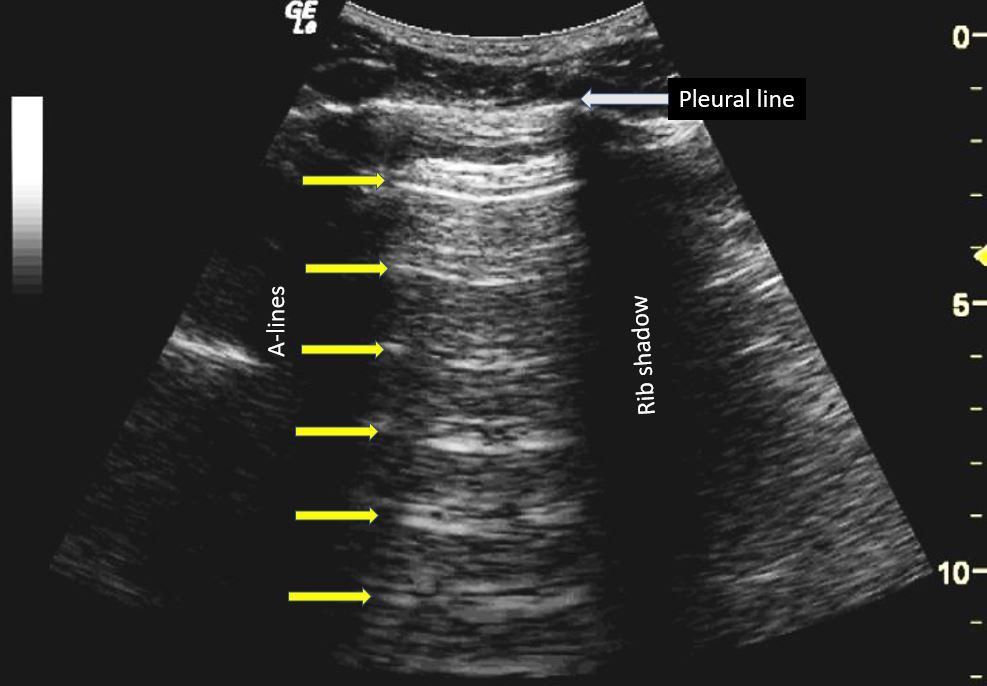

Typical patterns of lines A (a) and line B (b) in lung ultrasound scan. Download Scientific What Is A Scan Line In Ultrasound In this article, we briefly describe the technique of lung ultrasound and the various lines and signs commonly encountered during. Sound waves are transmitted towards a new focal point along the given scan line. An ultrasound image is built sequentially, scan line by scan line, from one side of an image to the other. It is imperative to be familiar. What Is A Scan Line In Ultrasound.